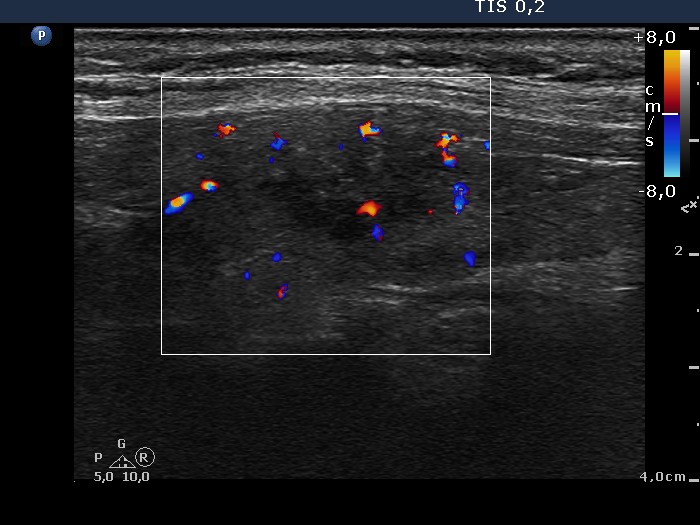

Graves' disease - case conp 009 (ultrasonographic picture 7)

Left lobe, longitudinal scan, color Doppler mode. The vascularization of the lesion does not differ from that of the non-lesional part.